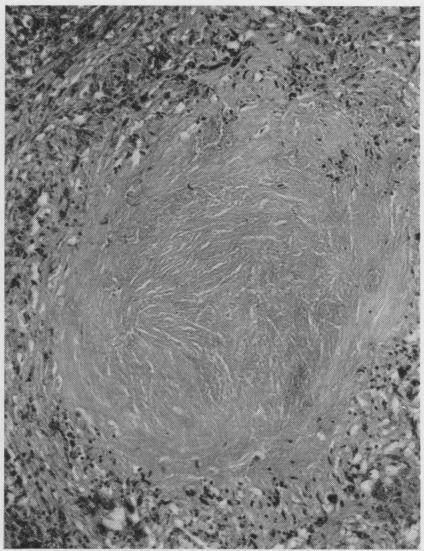

A histological study of the lungs in 52 cases of chronic beryllium disease.

Br J Ind Med. 1958 Apr;15(2):84-91. doi: 10.1136/oem.15.2.84.